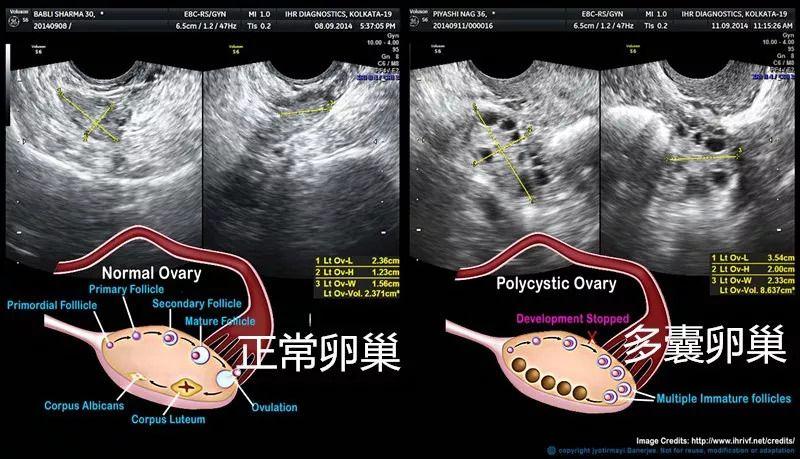

內分泌失調的女性,其中最常見的是多囊卵巢綜合症者,這種情況醫生一般會通過藥物治療促排卵,然後用超聲波監測患者的排卵情況。

目前最常用的方法是配合基礎體溫測定的陰道超聲波監測,它通過跟蹤監測優勢卵泡,最能客觀反映卵泡生長發育狀況,觀察是否有排卵,並同步反映子宮內膜的發育狀況。